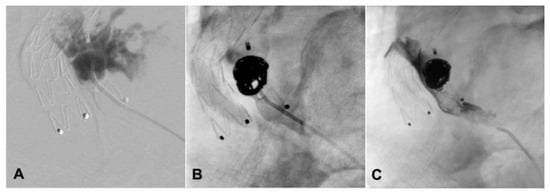

2. Case Presentation

| Present case | Angiographic + DUS guided, 18G needle, sheathless | Sac embolization with coils and a liquid embolic agent | Manual compression | None | 12-month CT scan, stable sac |